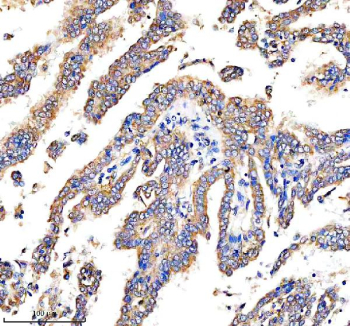

Immunohistochemical staining of DEPDC6/DEPTOR using anti-DEPTOR antibody. DEPDC6/DEPTOR was detected in a paraffin-embedded section of human stomach cancer tissue. Heat mediated antigen retrieval was performed in EDTA buffer (pH 8.0, epitope retrieval solution). The tissue section was blocked with 10% goat serum. The tissue section was then incubated with 2 ug/ml rabbit anti-DEPTOR antibody overnight at 4oC. Peroxidase Conjugated Goat Anti-rabbit IgG was used as secondary antibody and incubated for 30 minutes at 37oC. The tissue section was developed using an HRP secondary and DAB substrate.